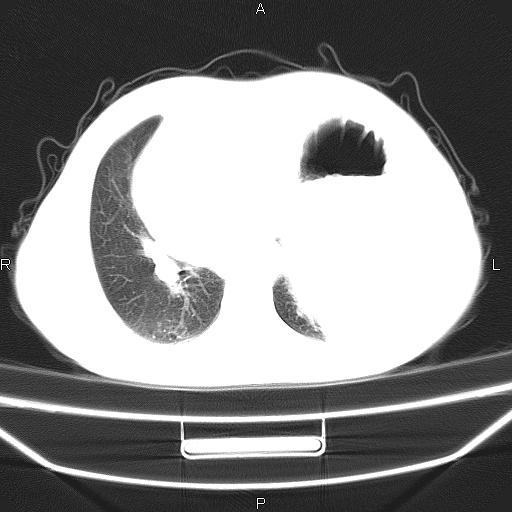

患者,男。50岁。近几日有咳嗽症状,无其他不适,既往病史无,考虑膈疝。请前辈们看看指导指导。

膈膨升,左下肺通气不良,膈肌好像还完整。

考虑左侧膈疝。

左侧膈疝。

符合隔膨升,膈肌较完整。